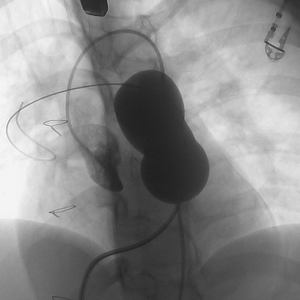

患者女性,21岁,19年前行法洛四联症矫治术,发现肺动脉重度关闭不全2年。术前影像学重建显示提示患者肺动脉最窄截面呈椭圆形,腰部径宽18-24mm。手术经胸小切口入路,术中通过经食道超声,球囊测量、科学评估肺动脉干后,考虑植入30# Salus介入肺动脉瓣。在TEE引导以及DSA造影下,经右室流出道穿刺植入瓣膜,术后TEE提示肺动脉介入瓣植入位置理想、固定良好,无瓣周漏及中央返流。

球囊评估